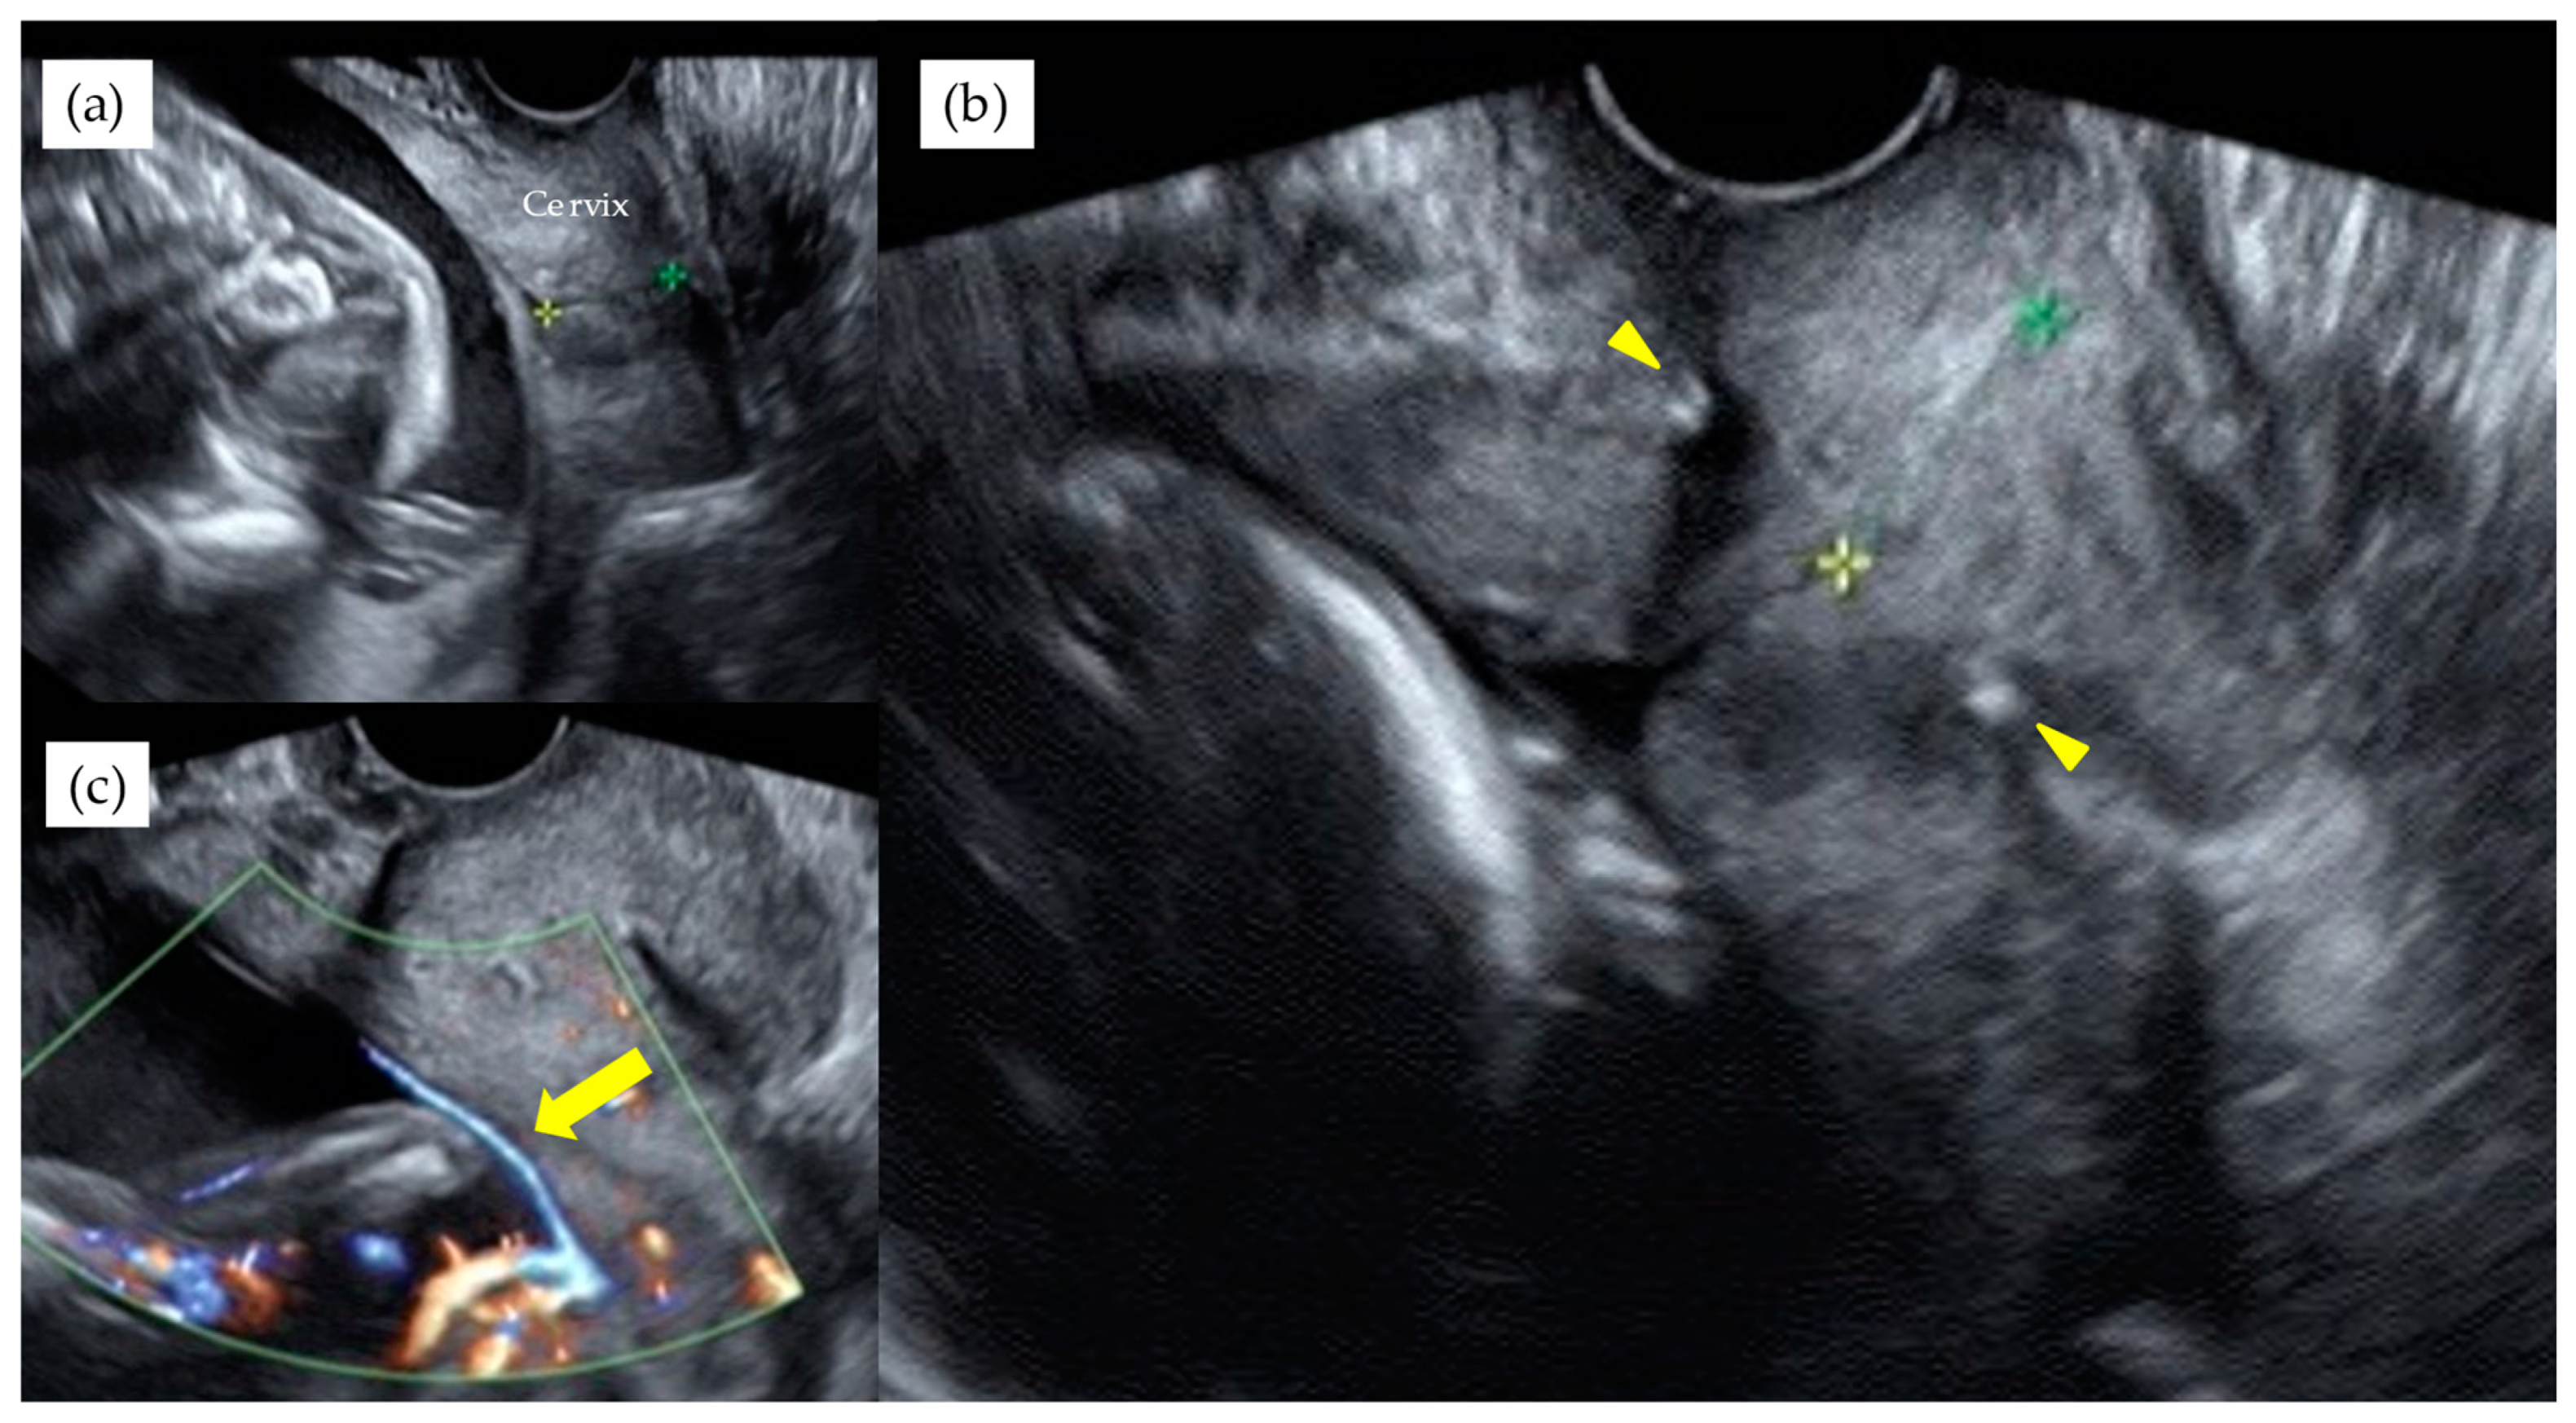

Figure 3. A monochorionic diamniotic pregnancy case of type 1 VP, with previous history of preterm singleton delivery at 34th GW, showed cervical length of 1.7 cm at 20th GW (a). Blood flow of fetal vessels were confirmed after cervical cerclage performed. Arrowheads indicate string of cervical cerclage (b). Arrows indicate vasa previa with color Doppler image after cervical cerclage (c). This patient delivered by CS at 31st GW. The yellow and green stars indicate the cervical length.

Table 3 shows the results of management and operative outcomes. In 31 cases (56.4%), including three twin pregnancies, tocolytic therapy was necessary (ritodrine hydrochloride and/or magnesium sulfate), and a steroid for fetal lung maturation was given in 9/13 cases (69.2%) delivered before the 34th GW. An abnormal fetal heart rate pattern without uterine contractions was detected in one case in the type 1 group, and this case exhibited a relatively thick artery near the internal ostium (Figure 2). Cervical cerclage via the McDonald technique was performed in two cases in the type 1 group. One of these cases was a singleton pregnancy at 20th GW and a cervical length of 2.1 cm, delivered by CS at 33rd GW. The other was a monochorionic-diamniotic pregnancy case at 20th GW and a cervical length of 1.7 cm, delivered by CS at 31st GW; this patient had a previous history of preterm singleton delivery at 34th GW. Blood flow of fetal vessels was confirmed post-cerclage in both cases (Figure 3). Resolution was observed in 12 cases (21.8%) in total. An emergent CS was performed in 25 cases with increased uterine contractions and in one case with an indication of hypertensive disorder of pregnancy; none of these cases experienced the premature rupture of membranes. Although the Ward technique was more frequently used in the non-type 1 group, the details as to operative outcome showed no significant difference between the two groups. The transection of the placenta to approach the fetus was not used in any of the cases. All cases underwent a cesarean section, even in those cases of resolution of VP.